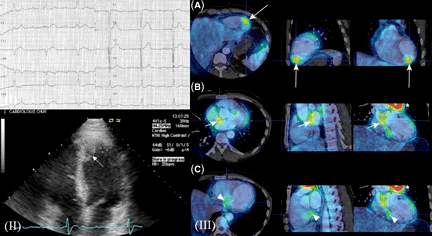

Chẩn đoán

Myxoma có thể chẩn đoán như sau:

+Từ các triệu chứng lâm sàng mà bênh nhân có;

+Dựa vào kết quả một điện tâm đồ;

+Thỉnh thoảng qua thông tim;

+Thỉnh thoảng qua sinh thiết nội tâm mạc hoặc cơ tim;

+Chụp nhấp nháy các cửa van tim;

+Chụp cắt lớp vi tính;

+Chụp cộng hưởng từ MRI;

+Chụp mạch tim.

U cơ vân và u sợi có thể chẩn đoán dựa trên nền các triêu chứng sinh ra.Nếu các triệu chứng cũng óc mặt kèm theo đặc điểmxơ hóa dạng củ (tuberous sclerosis), có thể có một khối u lành tính hiện diện. Điều này có thể xác định nhờ vào siêu âm tim hoặc chụp mạch tim (angiocardiography).

Các khối u ở tâm nhĩ, đặc biệt u myxoma ở tâm nhĩ phải, có thể chứa các cặn lắng calcium có thể nhìn thấy trong khi chụp X-quang.

Từ một ca bệnh: Cảnh giác “tức ngực, coi chừng u tim”

Thấy tức ngực, hụt hơi, nhiều người bỏ qua hoặc nghĩ là mắc bệnh phổi mà không ngờ thủ phạm là các khối u trong tim. Khối u ở tim có thể bắt gặp ở bất kỳ người ở độ tuổi nào. Các bác sĩ khuyến cáo, bệnh không thể dự phòng được, thường có tiên lượng xấu nên việc phát hiện, chẩn đoán và điều trị sớm có ý nghĩa quan trọng.

Dễ chẩn đoán nhầm!

Dù đã được phẫu thuật cắt bỏ khối u trong tim nhưng ông Đ., 40 tuổi, ở Nam Trực, Nam Định vẫn chưa hoàn hồn sau cơn thập tử nhất sinh. Ông Đ. kể, trước đây thỉnh thoảng thấy có cơn nặng ngực, hụt hơi, ông cứ chủ quan cho rằng do làm việc quá sức nên không đi khám. Gần đây, các cơn nặng, tình trạng tức ngực xuất hiện với tần suất nhiều hơn, người nhanh mệt, có những lúc đang nghỉ ngơi cũng thấy tim đập liên hồi, ngực nặng, khó thở. Đi khám, ông Đ. được chẩn đoán là suy nhược cơ thể, chỉ cần nghỉ ngơi, bồi bổ.

Sau thời gian điều trị, về nhà bệnh nhân lại bị sốt nhiều, ho khan và khó thở. Nguy hiểm hơn, ông Đ. thường xuyên bị ngất mỗi khi nằm. Cấp cứu tại Bệnh viện Tim Hà Nội, bệnh nhân được chẩn đoán có khối u nhầy 5 cm trong tim. Bác sĩ lý giải, khối u to lan gần hết tâm thất trái, sa vào hai lá gan gây cản trở đường vận chuyển máu vào tĩnh mạch phổi xuống tâm thất trái, đây là nguyên nhân khiến bệnh nhân khó thở, ngất lịm.

Thạc sĩ Ngô Chí Hiếu, Trưởng khoa Hồi sức cấp cứu, Bệnh viện Tim Hà Nội, cảnh báo, sự nguy hiểm của bệnh lý này là bệnh tiến triển âm thầm, triệu chứng ban đầu chỉ là các cơn tức ngực nên người bệnh dễ bỏ qua. Ngay cả khi bệnh phát triển ở giai đoạn nặng hơn với các biểu hiện như khó thở, ngất lịm..., nhiều trường hợp bị chẩn đoán nhầm với bệnh động kinh, hở van hai lá hoặc các bệnh lý của phổi.